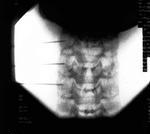

Con el paciente en decúbito supino y el cuello en ligera hiperextensión, se realizan 4 movimientos con el arco de rayos (Rx). Con el Rx en posición lateral, se identifica el nivel que se va a tratar. Cuando se ha identificado, se realiza un movimiento del Rx en posición oblicua hasta que se visualiza el foramen completamente. Cuando el foramen se ve claramente, se realiza un movimiento craneocaudal para eliminar el doble contorno del agujero que se va a tratar. Por último, con una proyección anteroposterior, se debe visualizar la punta de la aguja en la porción media de la articulación facetaria.